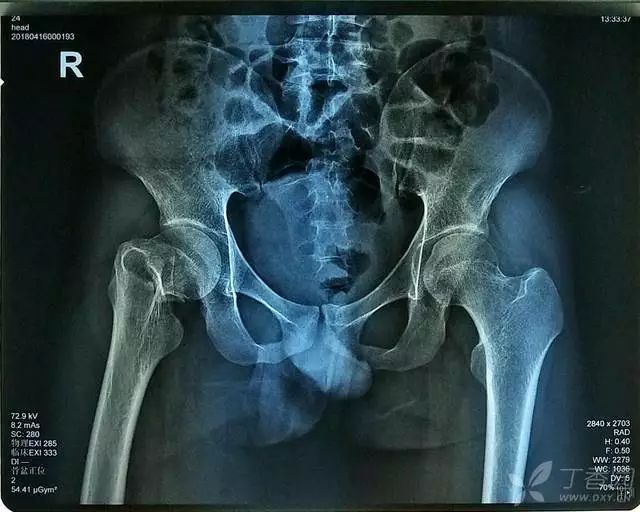

患者,男,23 岁,因「摔伤致右髋部肿痛、活动受限 6 小时」入院。

查体:右下肢无明显短缩,明显外旋畸形,右髋部轻度肿胀,未见明显皮下瘀斑、无皮肤擦伤等。右侧腹股沟中点固定压痛,右侧股骨大粗隆叩击痛及右下肢纵向叩击痛(+),右髋关节主被动活动均明显受限;右足踝等关节活动正常,右下肢末梢血运正常,各足趾的感觉、活动等均正常。

辅助检查:CT 检查提示右侧股骨颈骨皮质不连续,可见透亮骨折线及碎骨片影,断端错位、成角,周围软组织肿胀;右侧髋臼后下缘及左侧耻骨上支骨皮质不连续,断端未见明显错位;右侧髋臼后缘见类圆形稍低密度影,大小约 5*9 mm,边界清楚,边缘见硬化边;右侧髋关节在位,关节间隙未见明显变窄。

初步诊断:右股骨颈骨折(经颈型)